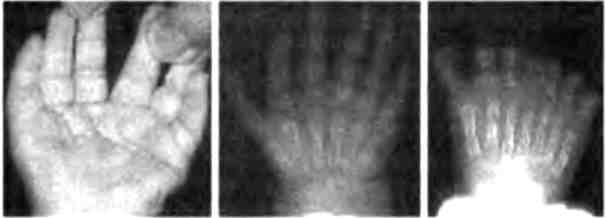

В коллекции Бэтсона присутствовали и человеческие уродства: здесь были люди с дополнительными ребрами, человек с лишними сосками, удивительная левая рука с восемью пальцами, расположенными симметричным образом, а также люди с лишними пальцами на одной или обеих руках (рис. 2.7). Этот последний дефект, называемый полидактилией, встречается не так уж редко, примерно у 5-17 из 10 000 живорожденных детей.

Рис. 2.7. Полидактилия у человека. Из книги У. Бэтсона "Материалы по изучению изменчивости", 1894.